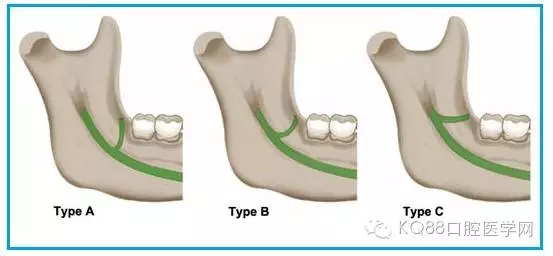

圖一 磨牙后區(qū)的形態(tài)學分類(綠色標示):

A.水滴形;

B.細長型;

C.三角形。